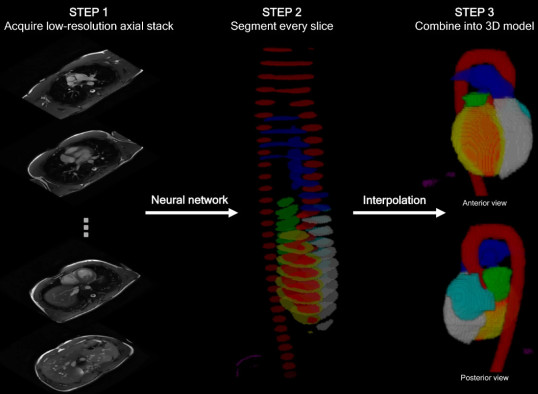

Automated cardiac MRI chamber quantification - LINK

James investigated whether deep learning of the sequences acquired in the first minutes of a scan could provide an early alert of abnormal features. It does this by segmenting out slices of the heart acquired at the start of a scan, and using these to reconstruct an accurate 3D model of the patient's heart. This solution is now in clinical use on the MRI scanners at Hammersmith Hospital.